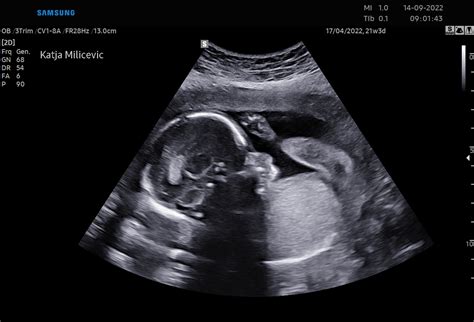

V 30. tednu nosečnosti je plod že precej razvit. Tehta med 1200 in 1400 grami in je dolg približno 39 cm. Količina maščobnega tkiva se povečuje, kar prispeva k bolj zaokroženi telesni obliki. Otrokov prebavni sistem je v veliki meri razvit, vendar še ni popolnoma zrel, kar lahko povzroči napenjanje in bolečine v trebuhu v prvih mesecih po rojstvu. Otrok se nahaja v položaju, kjer ima malo prostora za iztegovanje, zato leži v fetalnem položaju, s pokrčenimi nogami. Od tega tedna naprej postopoma izginjajo nežne dlačice (lanugo), ki prekrivajo njegovo telo. Znanstveno je dokazano, da lahko plod v tej fazi že občuti bolečino.